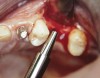

At the time of surgery, the tooth was extracted without harvesting any mucosal flap because the implant site was prepared by means of a pilot drill bur (Figure 13) and alternating osteotomes (Figure 14A and Figure 14B). The implant was positioned and showed primary stability. The implant was loaded 2 days after surgery. Then, splinted PFM crowns supported by custom gold abutments were delivered. At 6 months posttreatment, the radiograph revealed no bone resorption and the clinical result was optimal (Figure 15A and Figure 15B).

Figure 13  The drill bur was used to start the implant site preparation.

Figure 13

Figure 14a  Alternating osteotomes were used to prepare the implant site.

Figure 14a

Figure 14b  Alternating osteotomes were used to prepare the implant site.

Figure 14b